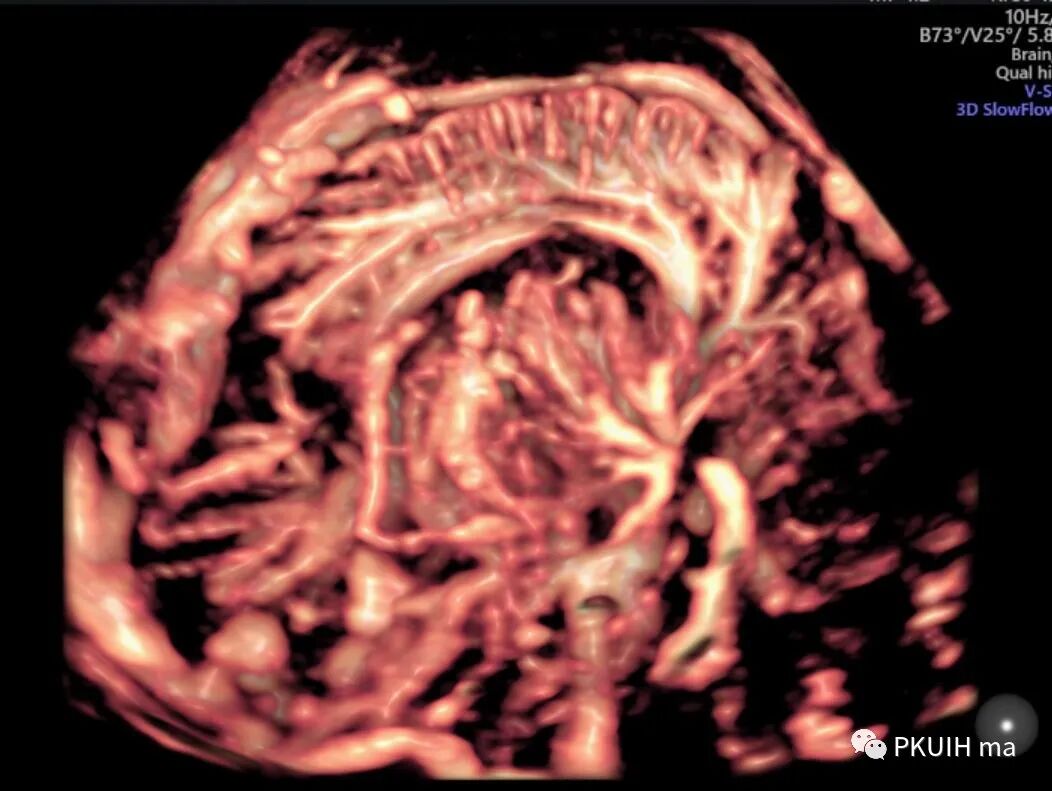

GE的SlowFlow功能还是有作用的。看看下面这几张,第一第二张图用CD和HD都不能完美的显示胎儿大脑Willis环,采用SlowFlow功能能够显示完整的颅底动脉环

通过这个血流成像前交通后交通都能完美显示

同样我们可以利用容积血流成像来显示颅底动脉环,看着更有立体感,但效果不如SlowFlow功能